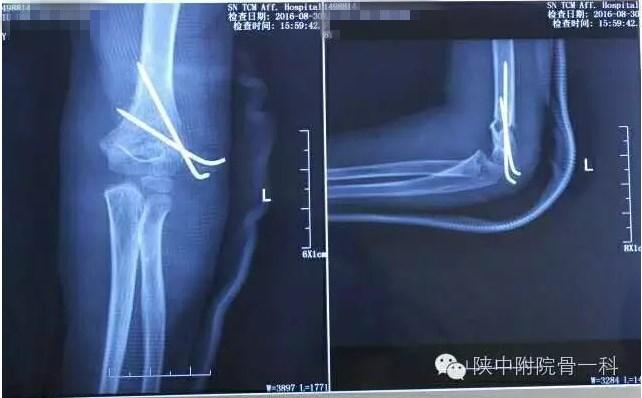

病案一:患儿XX,女,8岁,摔伤后左肘关节疼痛伴活动受限3小时入院。

诊断:Gartland Ⅱ型骨折

急诊行闭合手法复位克氏针内固定,术后X线片(下图)